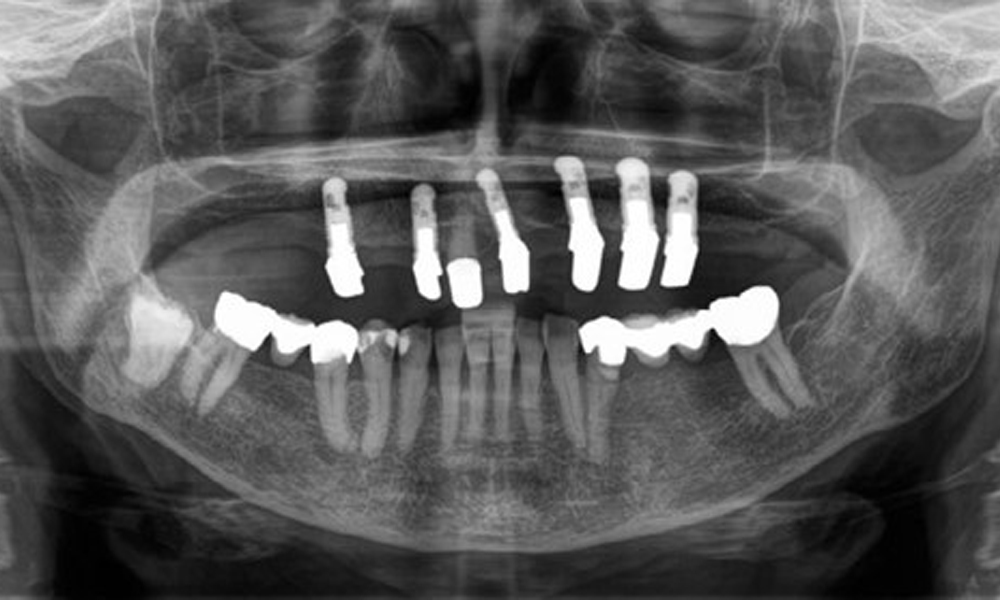

Рентгенологичните резултати показват частично беззъбо съзъбие с горночелюстни импланти за зъби 15, 13, 21, 23, 24, 25 и телескопична коронка на зъб 11. Налице са адекватни долночелюстни мостове, обхващащи участъци от 37 до 34 и от 45 до 47. Зъб 48 е засегнат. Има съмнения за вторичен кариес дистално на 43 и мезиално на 44. 44 е възстановен с нерадиационна облицовка на кухината. Налице е генерализирана хоризонтална костна загуба от приблизително 10-30 % и локализирана вертикална костна загуба, засягаща зъби 22 и 42 (фиг. 5).

Панорамна рентгенова снимка. Пациентът има пълен комплект постоянни зъби с генерализирана костна загуба между 10 и 30 %. Има рентгенологично съмнение за вторичен кариес на 44 и 43.

Фиг. 5: Панорамна рентгенова снимка. Пациентът има пълен комплект постоянни зъби с генерализирана костна загуба между 10 и 30 %. Има рентгенологично съмнение за вторичен кариес на 44 и 43.